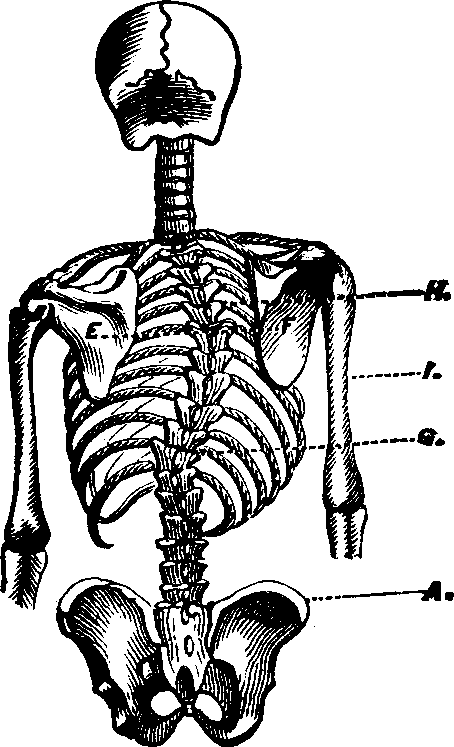

Fig. 10. Flexion, u, Uterus, B, Bladder.

Fig. 11. Version, u, Uterus, B, Bladder.

Flexions and Versions of the Womb. Flexion of the uterus, in which it is bent upon itself, as illustrated in Fig. 10, produces a bending of the cervical canal, constricting or obliterating it, and thus preventing the passage of spermatozoa through it. Version of the uterus [pg 710]in which its top, or fundus, falls either forward against the bladder (anteversion), as illustrated in Fig. 11, or backward against the rectum (retroversion), may close the mouth of the uterus by firmly pressing it against the wall of the vaginal canal, and thus prevent the passage of spermatozoa into the womb. 'The treatment of these several displacements will be considered hereafter. We may here remark, however, that they can be remedied by proper treatment. Our mechanical movements, manipulations, and kneadings are invaluable aids in correcting these displacements.